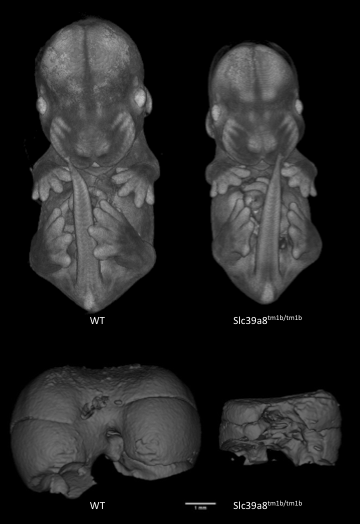

Slc39a8tm1b(EUCOMM)Wtsi

Solute carrier family 39 (metal ion transporter), member 8 encodes a protein that functions as a transporter for several divalent cations. Mutants show complete preweaning lethality with no homozygous pups observed, but are viable at least until E14.5. Micro-computed tomography (microCT) imaging at E14.5 revealed mutants were smaller and had cardiovascular abnormalities, such as ventral septum defects. It also revealed mutants lacked a sternum and had a small chest cavity and liver.

Slc39a8-null mutants are significantly smaller than WT littermates and have smaller livers.